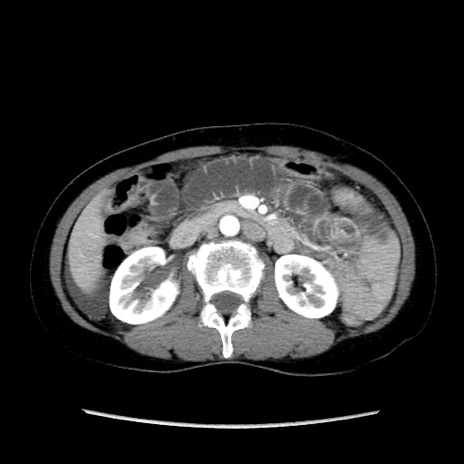

症例32(横断像)

【症例】40歳代 女性

【主訴】上腹部痛、嘔気・嘔吐

【現病歴】約9時間前頃から急に上腹部痛、嘔気、嘔吐が出現。改善しないため救急要請。

【既往歴】子宮頚癌(広汎子宮全摘術、放射線療法)、腸閉塞

【身体所見】腹部:平坦、軟、腸雑音亢進、上腹部を中心に腹部全体に圧痛あり。

【データ】WBC 8400、CRP 0.03